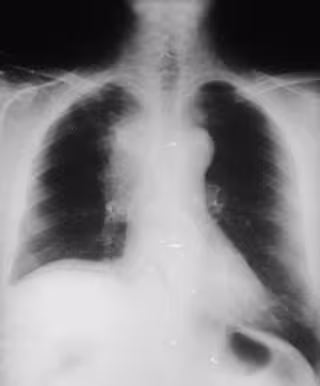

radiografía de pulmón, cáncer

La tasa de supervivencia global del cáncer de pulmón a los 5 años es sólo del 15 por ciento frente a otros como el de mama que tiene un 80 por ciento o el de colón con un 65 por ciento, informó la Sociedad Española de Neumología y Cirugía Torácica (SEPAR) con motivo de la celebración este jueves del Día Mundial del Cáncer.

En el año 2007 murieron en España 16.000 hombres y 2.500 mujeres debido al cáncer de pulmón y cada año, se diagnostican 20.000 nuevos casos siendo el cáncer de pulmón el segundo tipo de cáncer más frecuente entre varones tras el cáncer colon rectal, pero según afirma el SEPAR es el más letal. "La gravedad de la enfermedad se traduce en las desalentadoras cifras de supervivencia global a los cinco años. Si en el cáncer de mama la supervivencia se sitúa sobre el 80 por ciento o en el de colon en el 65 por ciento, el cáncer de pulmón apenas alcanza el 15 por ciento", explicaron.